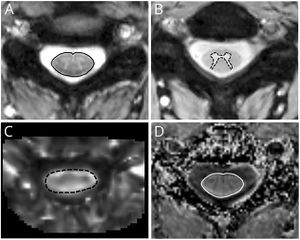

- 1.92 Quantitative Spinal Cord MRI in Radiologically Isolated Syndrome

Publication: PLoS One. 2018 Aug 16;13(8):e0202387. PMID: 30114235 | PDF Authors: Reynolds HM, Parameswaran BK, Finnegan ME, Roettger D, Lau E, Kron T, Shaw M, Chander S, Siva S. Institution: Department of Physical Sciences, Peter MacCallum Cancer Centre, Melbourne, Victoria, Australia. Abstract: PURPOSE: To explore the utility of diffusion and perfusion changes in primary renal cell carcinoma (RCC) after stereotactic ablative body radiotherapy (SABR) as an early biomarker of treatment response, using diffusion weighted (DWI) and dynamic contrast enhanced (DCE) MRI. METHODS: Patients enrolled in a prospective pilot clinical trial received SABR for primary RCC, and had DWI and DCE MRI scheduled at baseline, 14 days and 70 days after SABR. Tumours <5cm diameter received a single fraction of 26 Gy and larger tumours received three fractions of 14 Gy. Apparent diffusion coefficient (ADC) maps were computed from DWI data and parametric and pharmacokinetic maps were fitted to the DCE data. Tumour volumes were contoured and statistics extracted. Spearman's rank correlation coefficients were computed between MRI parameter changes versus the percentage tumour volume change from CT at 6, 12 and 24 months and the last follow-up relative to baseline CT. RESULTS: Twelve patients were eligible for DWI analysis, and a subset of ten patients for DCE MRI analysis. DCE MRI from the second follow-up MRI scan showed correlations between the change in percentage voxels with washout contrast enhancement behaviour and the change in tumour volume (ρ = 0.84, p = 0.004 at 12 month CT, ρ = 0.81, p = 0.02 at 24 month CT, and ρ = 0.89, p = 0.001 at last follow-up CT). The change in mean initial rate of enhancement and mean Ktrans at the second follow-up MRI scan were positively correlated with percent tumour volume change at the 12 month CT onwards (ρ = 0.65, p = 0.05 and ρ = 0.66, p = 0.04 at 12 month CT respectively). Changes in ADC kurtosis from histogram analysis at the first follow-up MRI scan also showed positive correlations with the percentage tumour volume change (ρ = 0.66, p = 0.02 at 12 month CT, ρ = 0.69, p = 0.02 at last follow-up CT), but these results are possibly confounded by inflammation. CONCLUSION: DWI and DCE MRI parameters show potential as early response biomarkers after SABR for primary RCC. Further prospective validation using larger patient cohorts is warranted. |

Baseline ADC map with tumour contour in red for patient 3 and associated histogram showing the frequency of ADC values in each MRI scan. ADC maps were read into 3D Slicer software and the tumour volume contoured directly onto ADC map image slices by an experienced radiologist. |